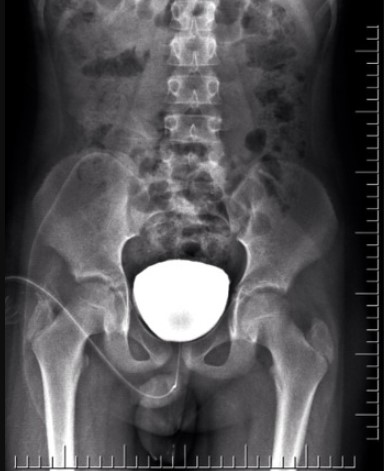

Tests done to investigate prostatic disorders may include, but are not limited to the following: urinalysis; intravenous urography; uroflowmetry; cystourethrography; and determination of the prostate-specific antigen (PSA) values. In addition, tests to evaluate creatinine levels, blood urea nitrogen (BUN), and phosphate and calcium levels may be done to determine if metastasis to the bone has occurred. Other diagnostic measures may include: prostatic biopsy; ultrasound; magnetic resonance imaging (MRI); and computed tomography (CT) scan.